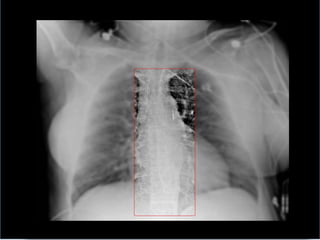

Confirmation of position

 arterial balloon waveform and pressures shown

 Chest x-ray or fluoroscopy

radiopaque tip lies in the 2nd intercostal spaces

just above the left main bronchus; lower end of

balloon should lie cephalad to the renal arteries